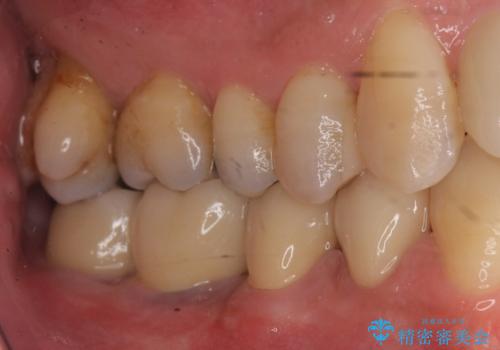

- 歯周病を気にして来院。

前歯の虫歯を治そうにも、歯並びの問題で難しい状態でした。

右下の奥歯も欠損しており、インプラント治療が必要な状態でした。